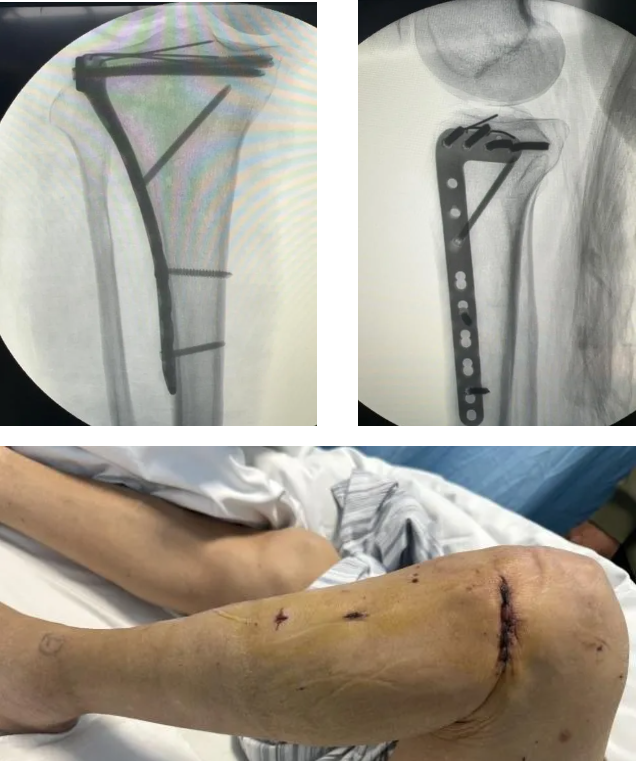

手术在 X 线透视导航下精准实施,团队仅于患者膝关节处作约 4 厘米小切口,借助特制撑开器充分暴露关节面,以顶棒精准复位塌陷软骨面,经细克氏针临时固定后,置入钢板,再通过 2 个仅 0.5 厘米的微型置钉孔完成螺钉固定。

整场手术行云流水,克氏针与螺钉精准锚定骨骼理想位置,既为骨折愈合提供坚实力学支撑、实现关节面解剖复位,又将创伤降至最低。术后采用美容皮内缝合技术处理切口,淡化疤痕,兼顾疗愈效果与外观美观。